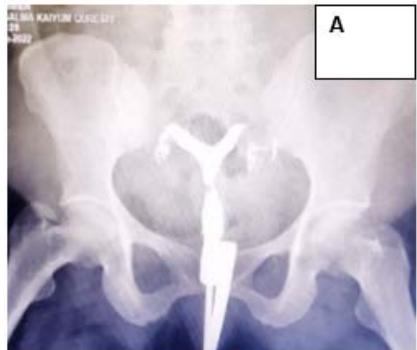

A 34-year-old female married for 9 years, with 4 spontaneous abortions at 3-4 months of gestation, presented with secondary infertility. USG showed Bicornuate uterus with almost equal right and left horns, communicating in the lower third of the uterus, s/o Bicornuate uterus, with HSG confirming the diagnosis. Post metroplasty, she had a successful pregnancy till term and underwent LSCS uneventfully. (Fig. 4)

Figure 4: A: HSG s/o Bicornuate uterus. B: Bicornuate uterus. C: Temporary ligation with Foley and opening uterine cavity. D and E: Anterior and posterior surface after suturing. F: Healed uterus as seen during Caesarean section.